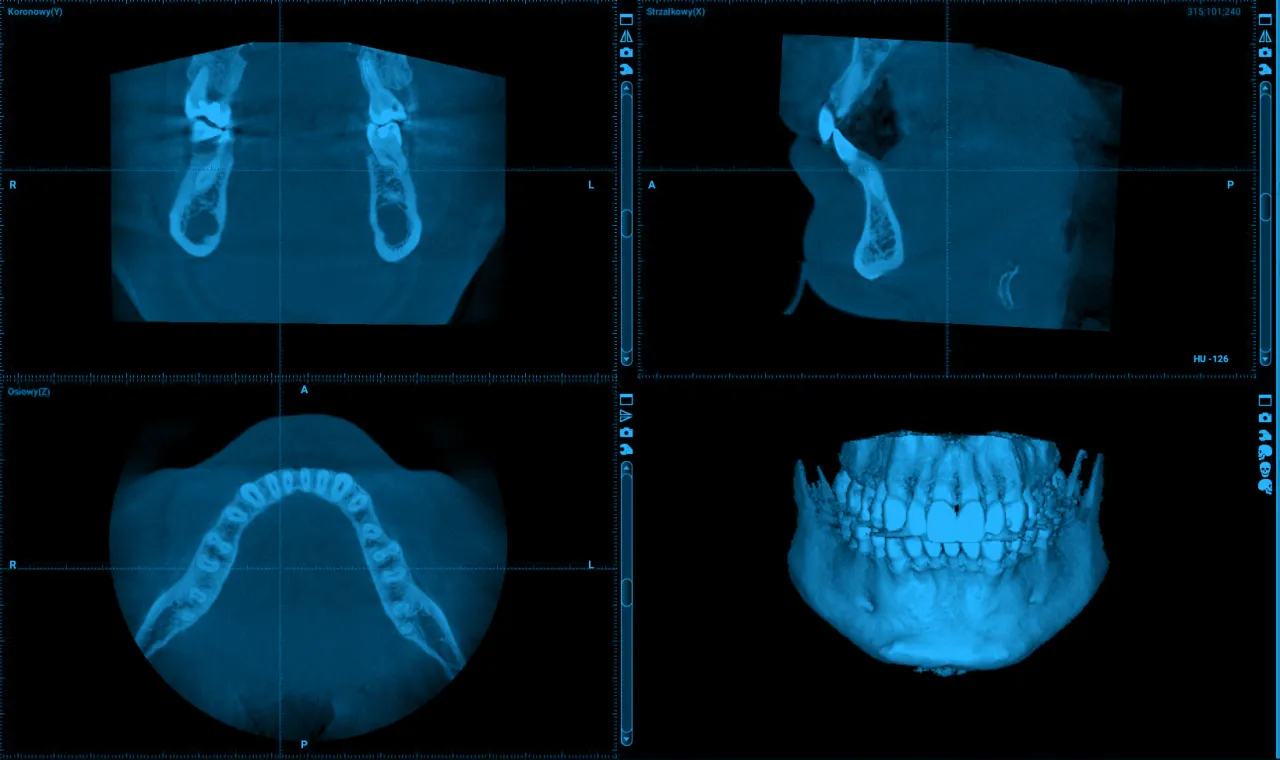

CBCT (tomografia stożkowa): Trójwymiarowy wymiar diagnostyki

CBCT, czyli tomografia komputerowa wiązki stożkowej, to najbardziej zaawansowane narzędzie diagnostyczne, które oferuje trójwymiarowy obraz struktur szczęki i żuchwy. W przeciwieństwie do tradycyjnych zdjęć RTG, które są dwuwymiarowe, CBCT pozwala mi zobaczyć zęby, kości, nerwy i zatoki w przestrzeni. Jest to niezwykle cenne w skomplikowanych przypadkach, na przykład przy planowaniu implantów (gdzie trzeba precyzyjnie ocenić ilość i jakość kości), w diagnostyce skomplikowanych złamań, torbieli, czy w endodoncji (leczeniu kanałowym), gdy chcę dokładnie zlokalizować dodatkowe kanały lub złamane narzędzia. To jak mapa 3D, która daje mi pełny obraz sytuacji.